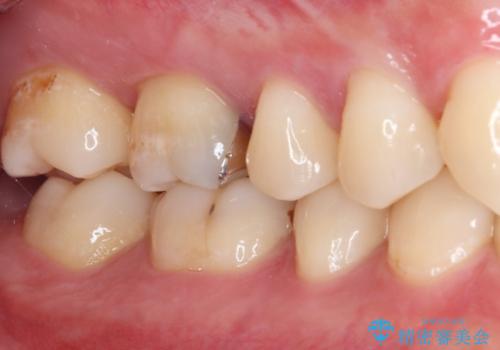

- 数年前他院にて治療した銀歯をやり替え希望の患者様です。

拡大鏡下で、銀歯、むし歯の除去を行い、セラミックインレーに適した形に整えました。